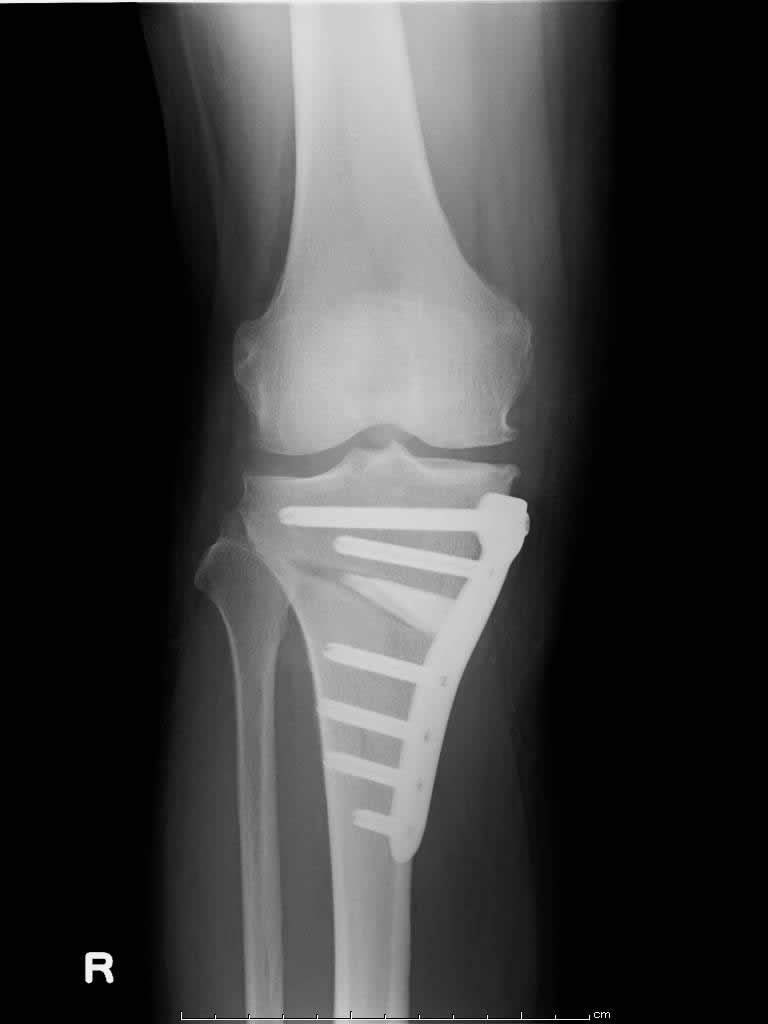

その他の変形性膝関節症の手術

高位脛骨骨切り術

変形性膝関節症の多くは、膝がO脚であるために膝の内側の軟骨が減ることで痛みが生じます。

すねの骨(脛骨)を切って、少しX脚に矯正する手術です。

この手術を行うと膝の内側にかかっていた体重が膝の外側にかかるようになり、痛みが軽減または消失します。

近年では中高年でスポーツをされる方が増えており、そういった方や若年者では自分の膝関節を温存する目的で骨切り術を行っています。